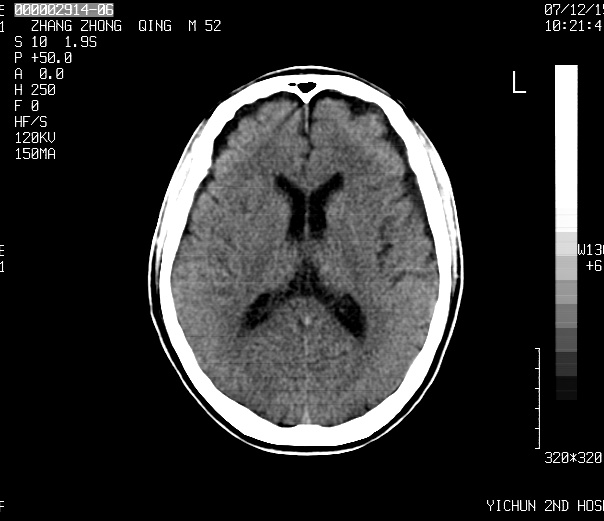

1、四叠体脂肪瘤;

2、双侧额、顶部硬膜下积液。